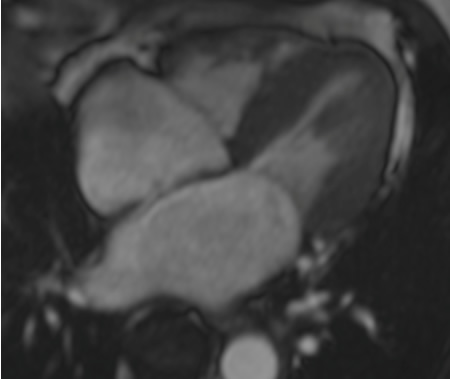

[Figure caption and citation for the preceding image starts]: CMR (cardiac magnetic resonance) imaging demonstrating restrictive cardiomyopathy with bi-atrial dilation and mild concentric left ventricular hypertrophyFrom the collection of Dr Jessica Webb; used with permission [Citation ends].

[Figure caption and citation for the preceding image starts]: CMR (cardiac magnetic resonance) imaging confirming left atrial enlargement and left ventricular hypertrophy (LVH)From the collection of Dr Jessica Webb; used with permission [Citation ends].